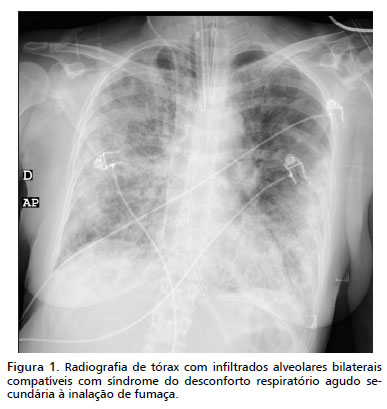

Durante a internação precoce, a paciente desenvolveu hipoxemia persistente com razão PaO²/FiO² <200 e radiografia de tórax com infiltrados alveolares bilaterais compatíveis com síndrome do desconforto respiratório agudo secundária à inalação de fumaça (Figura 1). Instituiu-se ventilação mecânica protetora (VT ~6mL/kg de peso previsto, PEEP 10-12cmH2O) e ajustes conforme gasometrias seriadas. O suporte intensivo incluiu ressuscitação volêmica orientada pela fórmula de Parkland e metas de débito urinário ≥0,5mL/kg/h, monitorização invasiva arterial e venosa e suporte nutricional enteral precoce. A fibrobroncoscopia realizada no 2º dia evidenciou edema e hiperemia de pregas vocais, sem necessidade de desbridamento endobrônquico ou realização de lavagem broncoalveolar extensiva, por decisão clínica face à estabilidade das secreções e risco de dessaturação.

Limitações deste relato incluem o caráter único do caso (evidência de nível 5), que não permite conclusões definitivas sobre eficácia comparativa, ausência de dosagem sérica imediata de cianeto e a impossibilidade de estabelecer causalidade direta entre doses adicionais de hidroxocobalamina e normalização do lactato. Ainda assim, o detalhamento cronológico e a inclusão de dados radiográficos (Figura 1) e do algoritmo de decisão (Figura 2) podem contribuir para orientar equipes que enfrentem situações semelhantes.